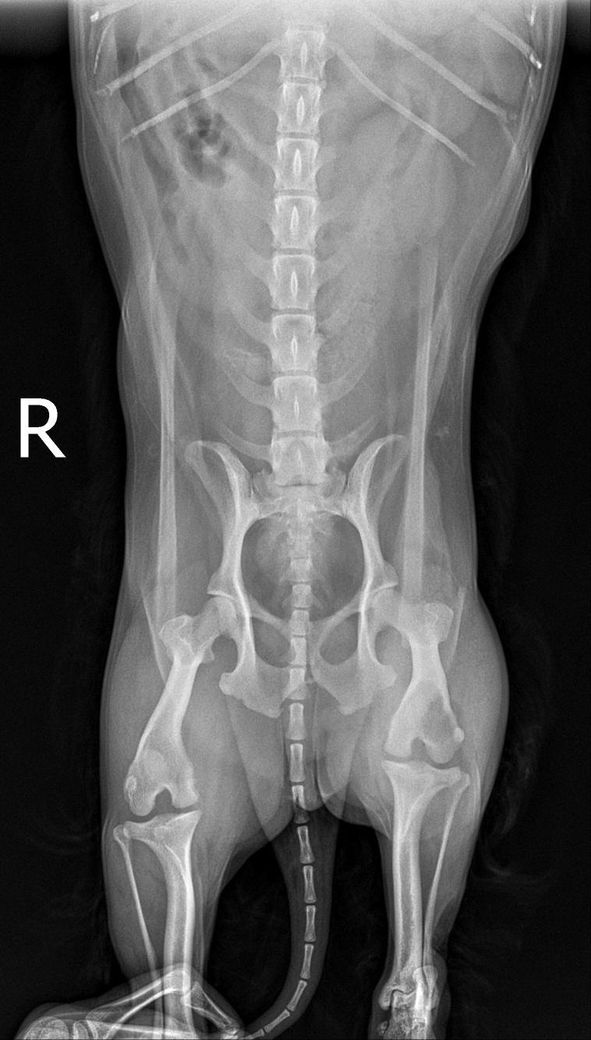

10년된 강아지가 아파서 밥도못먹고 낑낑대고 다리도 절뚝거리고하는데 병원가서 검사도 받고 다했는데 괜찮다고하네요 근데 x-ray사진을 봤을때 제가봐도 이상하고 다른사람들이 봐도 이상하다고 보는데 왜 의사만 괜찮다고 할까요?? 혹시 사진보시고 뭐가 문제인건지 알 수

있을까요??

해당 부위에 종괴가 있는것으로 보이니 정밀 초음파 검사나 CT촬영이 가능한 동물병원에 데려가서 다시 검진 받으시기 바랍니다.